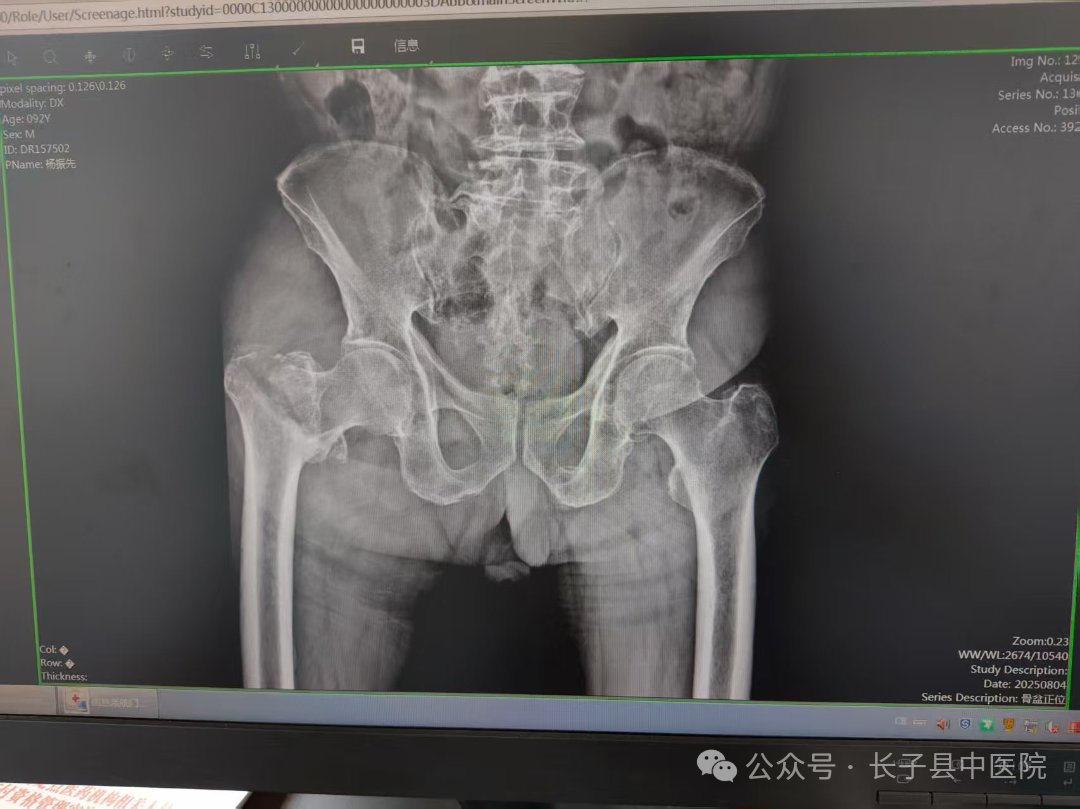

5小时前,杨大爷在家中不慎摔倒,当即出现右髋部剧烈疼痛,右下肢无法负重行走。这一突发状况让家属身心俱疲,他们第一时间将杨大爷送至我院就诊。门诊影像学检查显示,杨大爷确诊为“右侧股骨粗隆间骨折”,医院随即开通绿色通道,将其收治骨科住院治疗。

面对如此复杂的情况,我院骨伤科主任李志强及主管大夫李伟与医护团队(骨科全体、内科、手术麻醉科、彩超室、医务科)进行了周密的术前讨论,共同探讨最佳的手术方案,经过反复权衡,最终确定了手术策略,完善相关检查后,排除手术禁忌证,行右股骨粗隆间骨折闭合复位PFNA内固定术,手术时间仅用了1小时,术中、术后输血共800ml,以补充血容量,纠正贫血,手术过程严格无菌操作,在骨折复位时,确保对位对线良好。整个手术过程顺利。